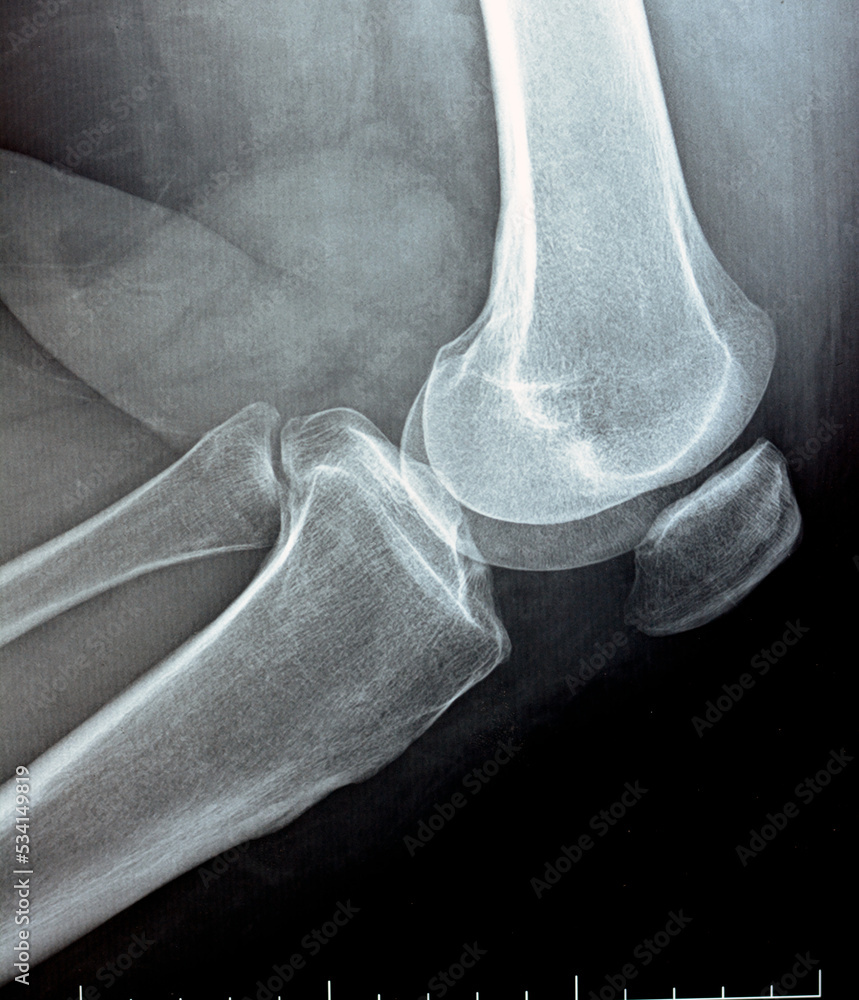

Radiograph of the elbow showing severe jointspace narrowing and What Is Joint Narrowing joint space narrowing occurs when the space between two bones that form a joint narrows. joint space narrowing (jsn) refers to the space between the bones in a person's joints. In stage 1, a person may not notice any symptoms. osteoarthritis (oa) is a common form of arthritis that often affects the knee. table of contents.. What Is Joint Narrowing.

From stock.adobe.com

plain x ray on knee joint showing joint space narrowing and Subchondral What Is Joint Narrowing joint space narrowing (jsn) refers to the space between the bones in a person's joints. Sometimes people are searching the term medial joint space narrowing because they are nervous. Knee pain due to arthritis can be disabling, or the pain can be mild. osteoarthritis (oa) is a common form of arthritis that often affects the knee. joint. What Is Joint Narrowing.